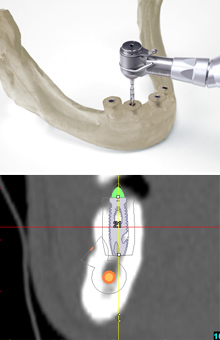

「サージカルガイド」

インプラントを埋め込むためには、ドリルで顎の骨に穴を開ける必要があります。サージカルステントとは、インプラントを埋め込む位置を確認するために使われる透明樹脂の型です。サージカルガイドとはドリルを適切な位置に導くためのインプラント手術支援用のガイドです。

サージカルで、CT撮影した患者様の顎の骨の3次元データをもとに、SimPlantRを用いて最適な埋め込み位置をシミュレーションし、高い精度のサージカルガイドを製作します。

これにより、安心・安全なインプラント治療を実現します。